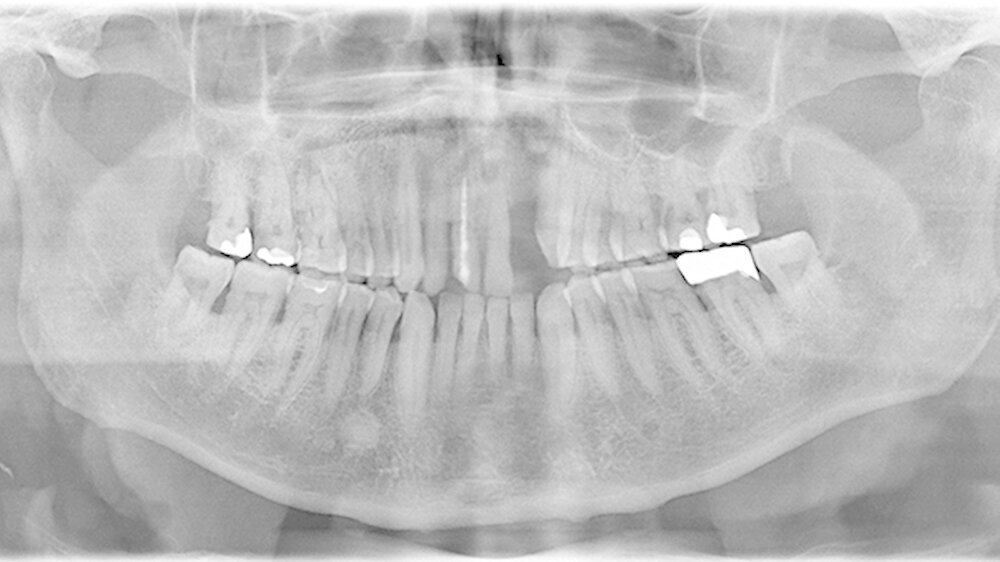

Ein 80 Jahre alter Patient stellt sich im September 2016 in der Poliklinik mit der Bitte um festsitzende Versorgung der Frontzahnlücke in Regio 22 vor (Abbildungen 1 und 2) Der Zahn 22 musste vor etwa einem Jahr parodontal bedingt extrahiert werden. Seitdem war diese Lücke durch einen Interimsersatz versorgt. Nach klinischer und röntgenologischer Befundung stellt sich schnell die Problematik dar, die im Rahmen der Versorgung dieser Frontzahnlücke auftreten wird.

Weiterhin werden eine Therapie-bedürftige Karies an 17 und ein apikal beherdeter 16 diagnostiziert, deren Behandlung ebenfalls durchgeführt wird.

Die Versorgung der Frontzahnlücke in Regio 22 wird intensiv mit dem Patienten diskutiert. Aufgrund des absoluten Mangels an ortsständigem Knochen, des hohen Patientenalters sowie der eher mäßigen Mundhygiene scheidet eine Implantation mit Knochenaugmentation aus. Hinzu tritt die starke, vor allem im Frontzahngebiet ausgeprägte Parodontitis. Ein langfristiger Erhalt des endodontisch versorgten 11 sowie des stark parodontal kompromittierten 21 erscheint unrealistisch.